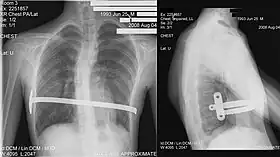

Chest x-rays are also useful in the diagnosis. The chest x-ray in pectus excavatum can show an opacity in the right lung area that can be mistaken for an infiltrate (such as that seen with pneumonia).[20] Some studies also suggest that the Haller index can be calculated based on chest x-ray as opposed to CT scanning in individuals who have no limitation in their function.[21]